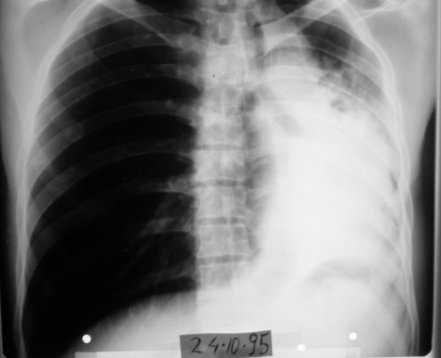

1995 yılında küçük hücreli anaplastik karsinom teşhisi konulan 31 yaşındaki erkek hasta, kemoterapiyi reddederek immünomodülatör tedavi ile 7 ayda tam iyileşme sağladı. Şiddetli ağrıları sadece 12 günde kayboldu ve röntgende tümör tamamen ortadan kalktı.

1995: 31 yaşındaki erkek hasta öksürük, ateş ve sırt ağrısı ile başvurdu.

24 Ekim 1995: Hasta uzman hekime getirildi.

Tedavi Protokolü: Haftada 6 gün, 4 mg immünomodülatör aşı

12 gün sonra: Şiddetli ağrıları tamamen kayboldu.

6 Kasım 1995 (2 hafta sonra)

Röntgende kitle küçülmüş durumda görüldü.

1996 Mayıs (7. Ay)

Röntgen tümörün tamamen kaybolduğunu gösterdi.

Radyolojik Kanıt: Röntgende tümör tamamen kayboldu